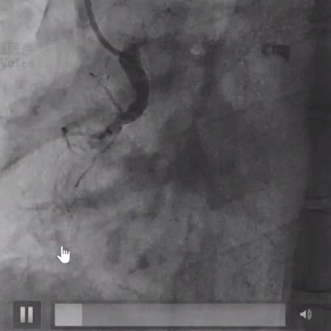

西安交通大学第一附属医院乌宇亮教授介绍到患者为一名67岁男性,主因“活动后胸闷气短1月、加重1周”入院,冠脉造影显示LAD及LCX近中段中重度狭窄,向RCA提供侧支循环;RCA异常开口于升主动脉,自近段闭塞,全程可见钙化影,CTO入口处有较大分支,出口处血管相对健康且粗大。

分析病变特征后术者决定首先启动正向策略,在Corsair微导管支撑下导丝进入内膜下,换用SASUKA导管辅助后通过平行导丝技术将Conquest pro导丝送入真腔,但无法通过RCA 3段重度狭窄处,在旋转Corsair时Corsair头端损毁并抱紧导丝。随后术者换用新的微导管和导丝,多次尝试后最终成功将1.0*10mm Firefighter™球囊送入闭塞段以远,以16atm反复扩张后球囊爆裂,为后续器械通过打开了通道。最终成功在闭塞段植入2枚支架。

RCA自近段闭塞

RCA植入支架后

对于这一病例,广东省人民医院杨峻青教授认为RCA异位开口导致强支持的Guiding难以到位。术者合理使用各种技术,配合合理的器械选择,很好完成手术。小尺寸的Firefighter™球囊通过性好,多次扩张后仍保持优越性能,帮助手术成功。